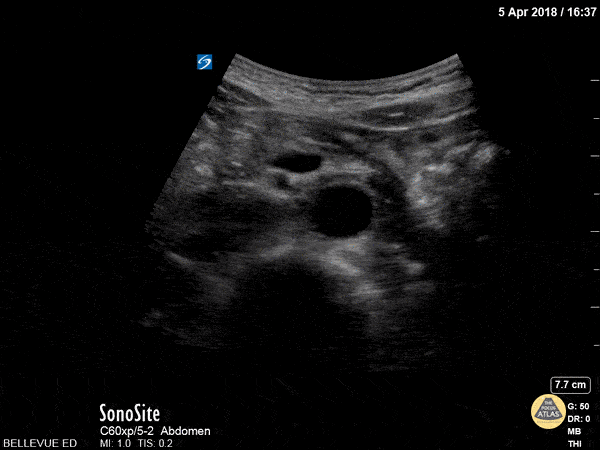

distalaorta